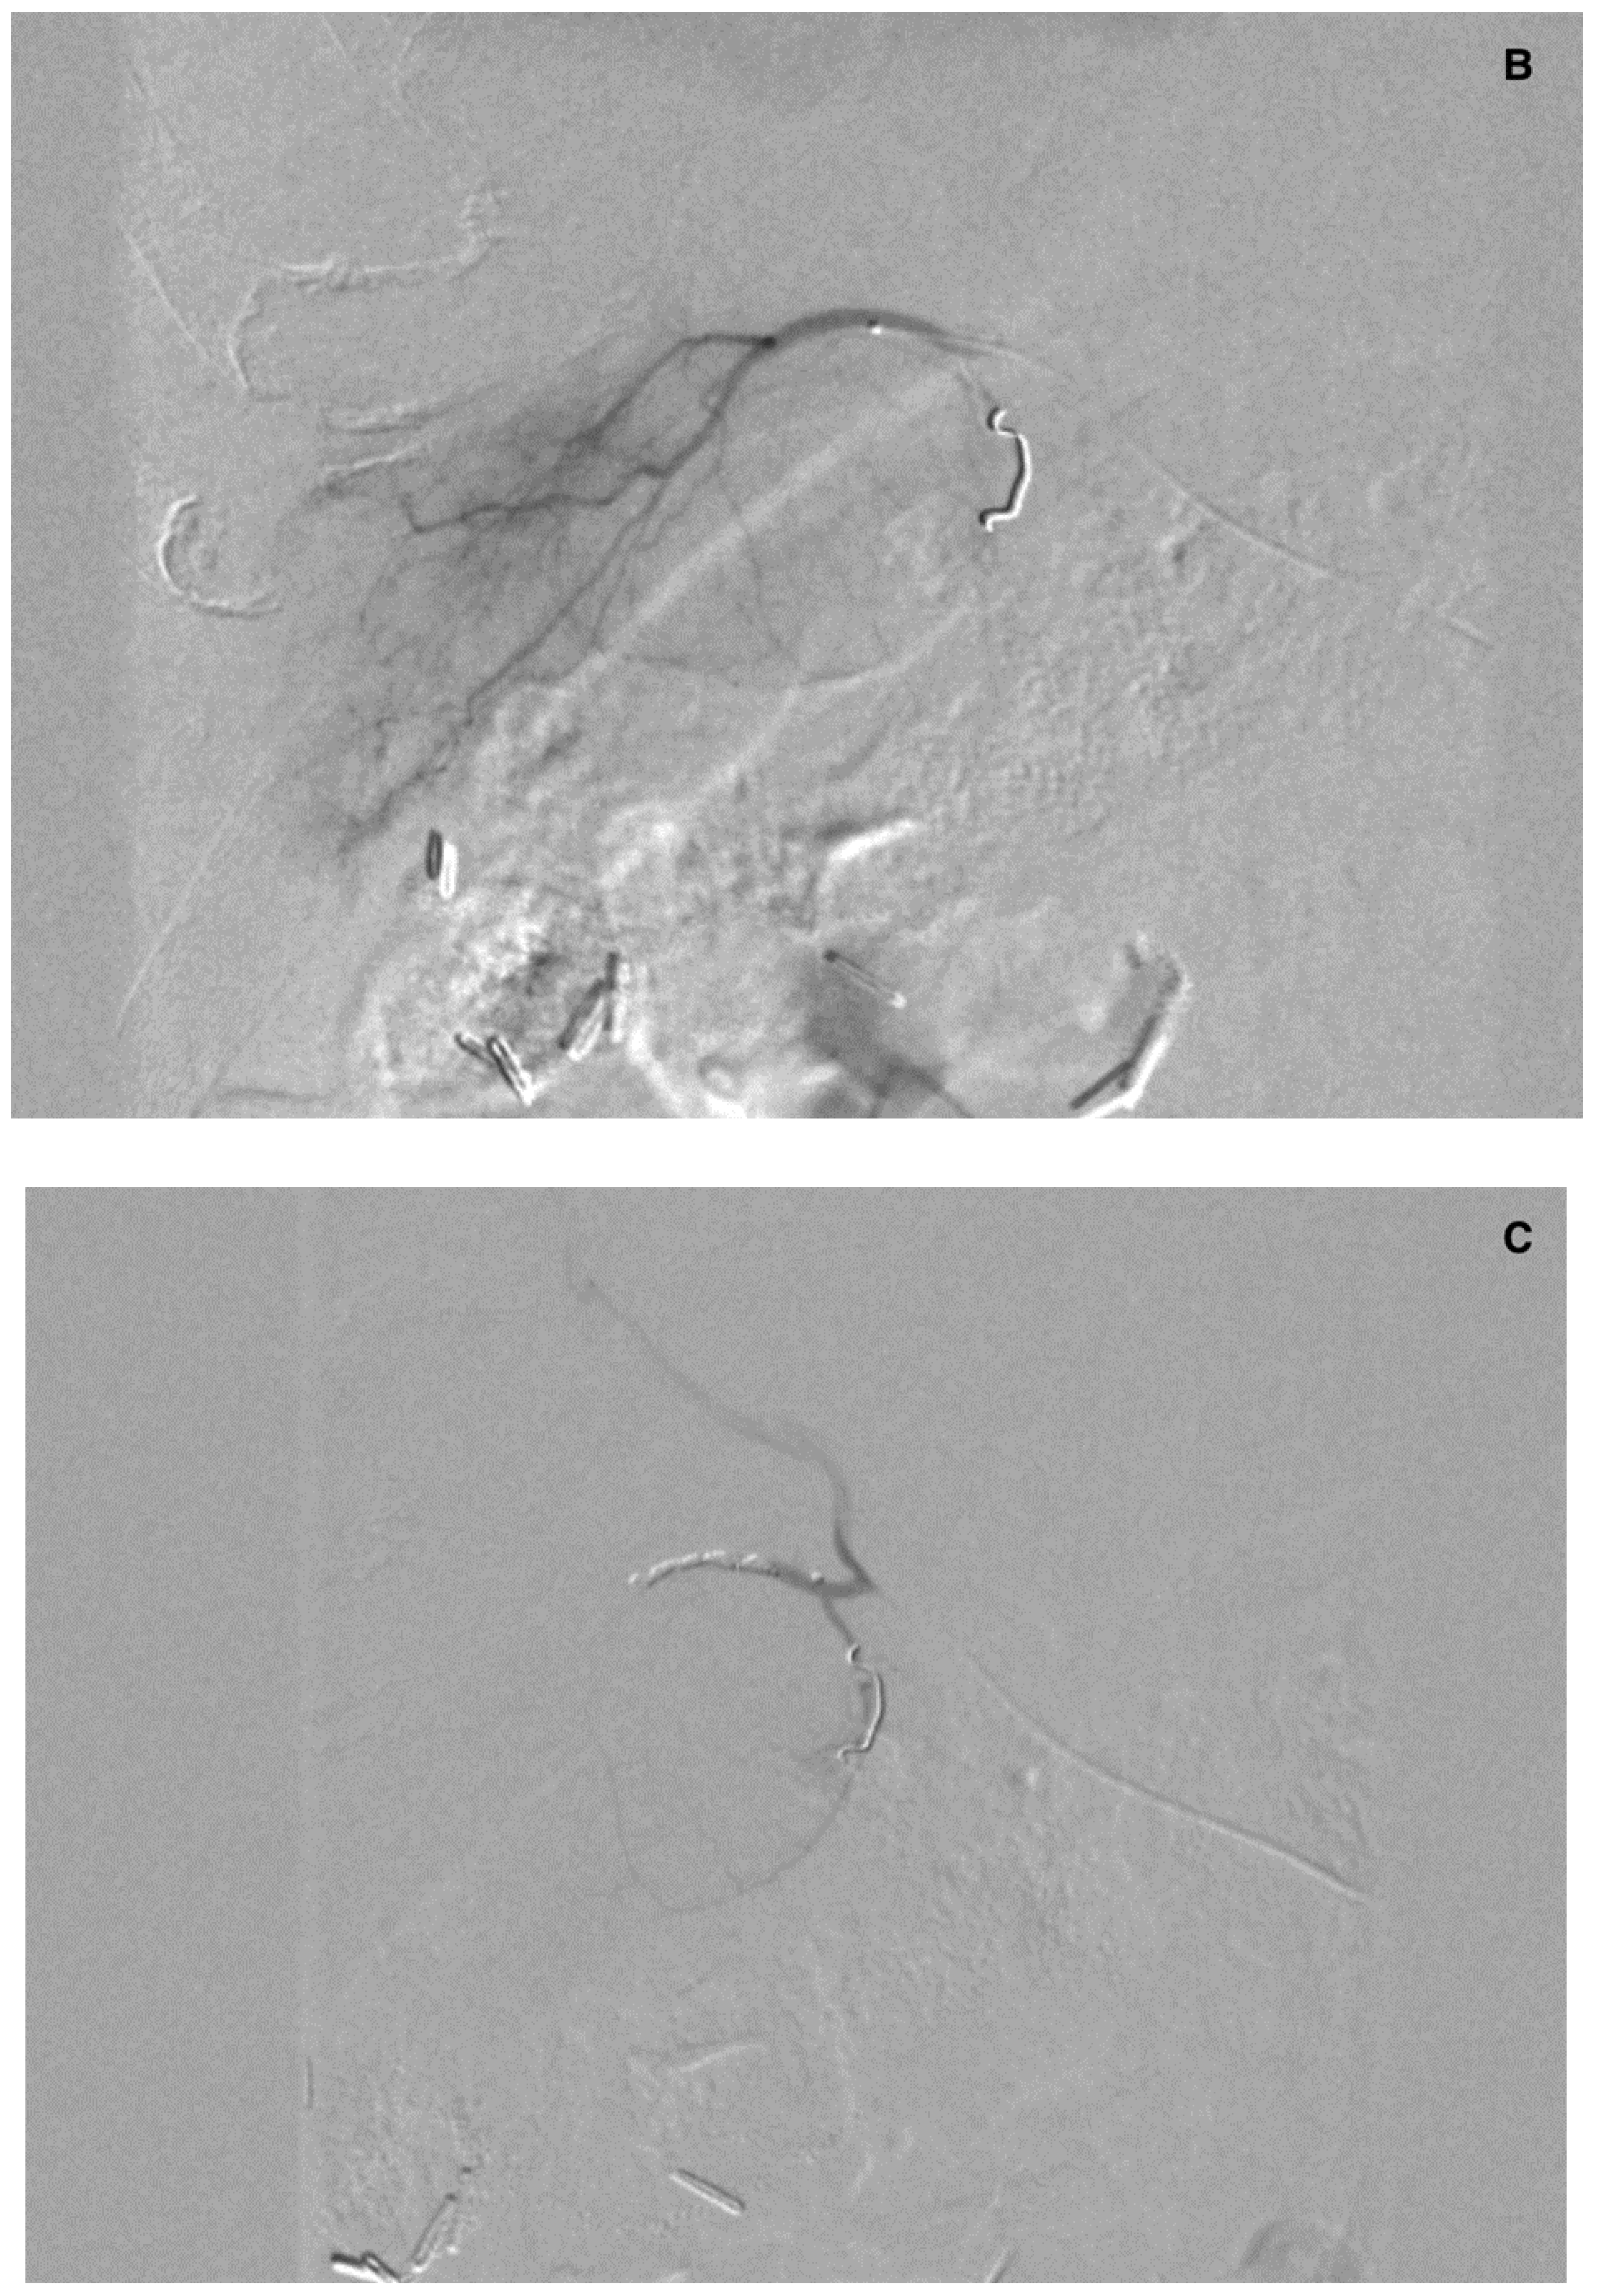

Figure 6.

(A) Angiogram of the left hepatic artery showing falciform artery travelling medially beyond the margin of the liver. (B) Its presence was confirmed on Dyna-CT and showed contrast enhancement of the abdominal wall (arrows) (C), and on SPECT/CT after 99mTc-MAA injection (D) (crosshairs).